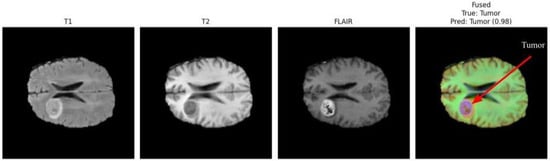

Figure 3 and Figure 4 present a visual comparison of the individual MRI modalities (T1, T2, FLAIR) and their fused representations used as inputs to the proposed multimodal CNN. Each modality contributes distinct and complementary tissue contrasts, while the fused image integrates these characteristics to enhance tumor visibility and support accurate detection. Arrows in the fused images highlight the regions identified as tumorous by the classifier, demonstrating the system’s ability to localize pathologies with high confidence.

T1-weighted images offer high anatomical detail, providing sharp structural boundaries useful for identifying mass effects and tissue displacement. T2-weighted images emphasize fluid accumulation and edema, capturing peritumoral changes. FLAIR suppresses cerebrospinal fluid signals, increasing contrast around lesions located near ventricles and cortical sulci. The fused representation consolidates these complementary features into a single enhanced image, improving tumor delineation and facilitating more reliable classification.

In Figure 3, the arrow in the fused image indicates the detected tumor region, which the model identifies with a confidence score of 0.98. This demonstrates the strong contribution of multimodal fusion toward achieving precise tumor localization, even when tumors exhibit irregular morphology or subtle contrast patterns.

Figure 3. Comparison of T1, T2, FLAIR, and fused MRI inputs. The fused representation integrates complementary contrast patterns, improving tumor visibility and structural delineation.